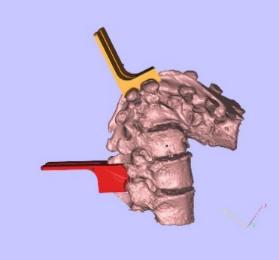

患者早年创伤导致严重脊柱后凸,采取手术方案。切除融合段脊柱后,采用定制化椎间融合器,并使用自体骨进行后路固定。针对手术方案进行病灶模型和截骨导板模型的3D打印制作。

案例中病人的腰部脊柱发生严重畸形,进而影响神经系统,急需进行脊柱矫形术,恢复正常的脊柱形态。

畸形的脊柱 手术方案

建模过程:

根据手术方案中的脊柱形态进行测量,定制个性化的假体和截骨导板。

需要截骨的平面

截骨导板放置位置